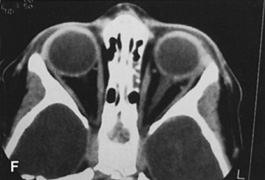

Valuable information about the nature and extent of an orbital pathologic process is provided by imaging studies such as computed tomography (CT) scan, magnetic resonance imaging (MRI), and orbital echography. Better spatial resolution, ready accessibility, and lower cost make CT the preferred choice for orbital imaging in most cases. Orbital fat provides a natural contrast between most adjacent orbital structures on CT scanning, and orbital bones are visualized well. Computed tomography is essential for evaluation of the orbital bones because they cannot be imaged with MRI. Direct coronal or sagittal images are important to identify the relationship of a lesion to the optic nerve so that the surgical approach can be planned to avoid traversing the optic nerve (Fig. 1).

Fig. 1. A. Axial CT scan demonstrating a large, well-encapsulated lesion in the orbital apex. Coronal (B) and sagittal (C) scans demonstrate that the mass lies inferior and medial to the optic nerve within the intraconal space. This information is useful in planning the surgical approach to the mass, which should avoid traversing the optic nerve.